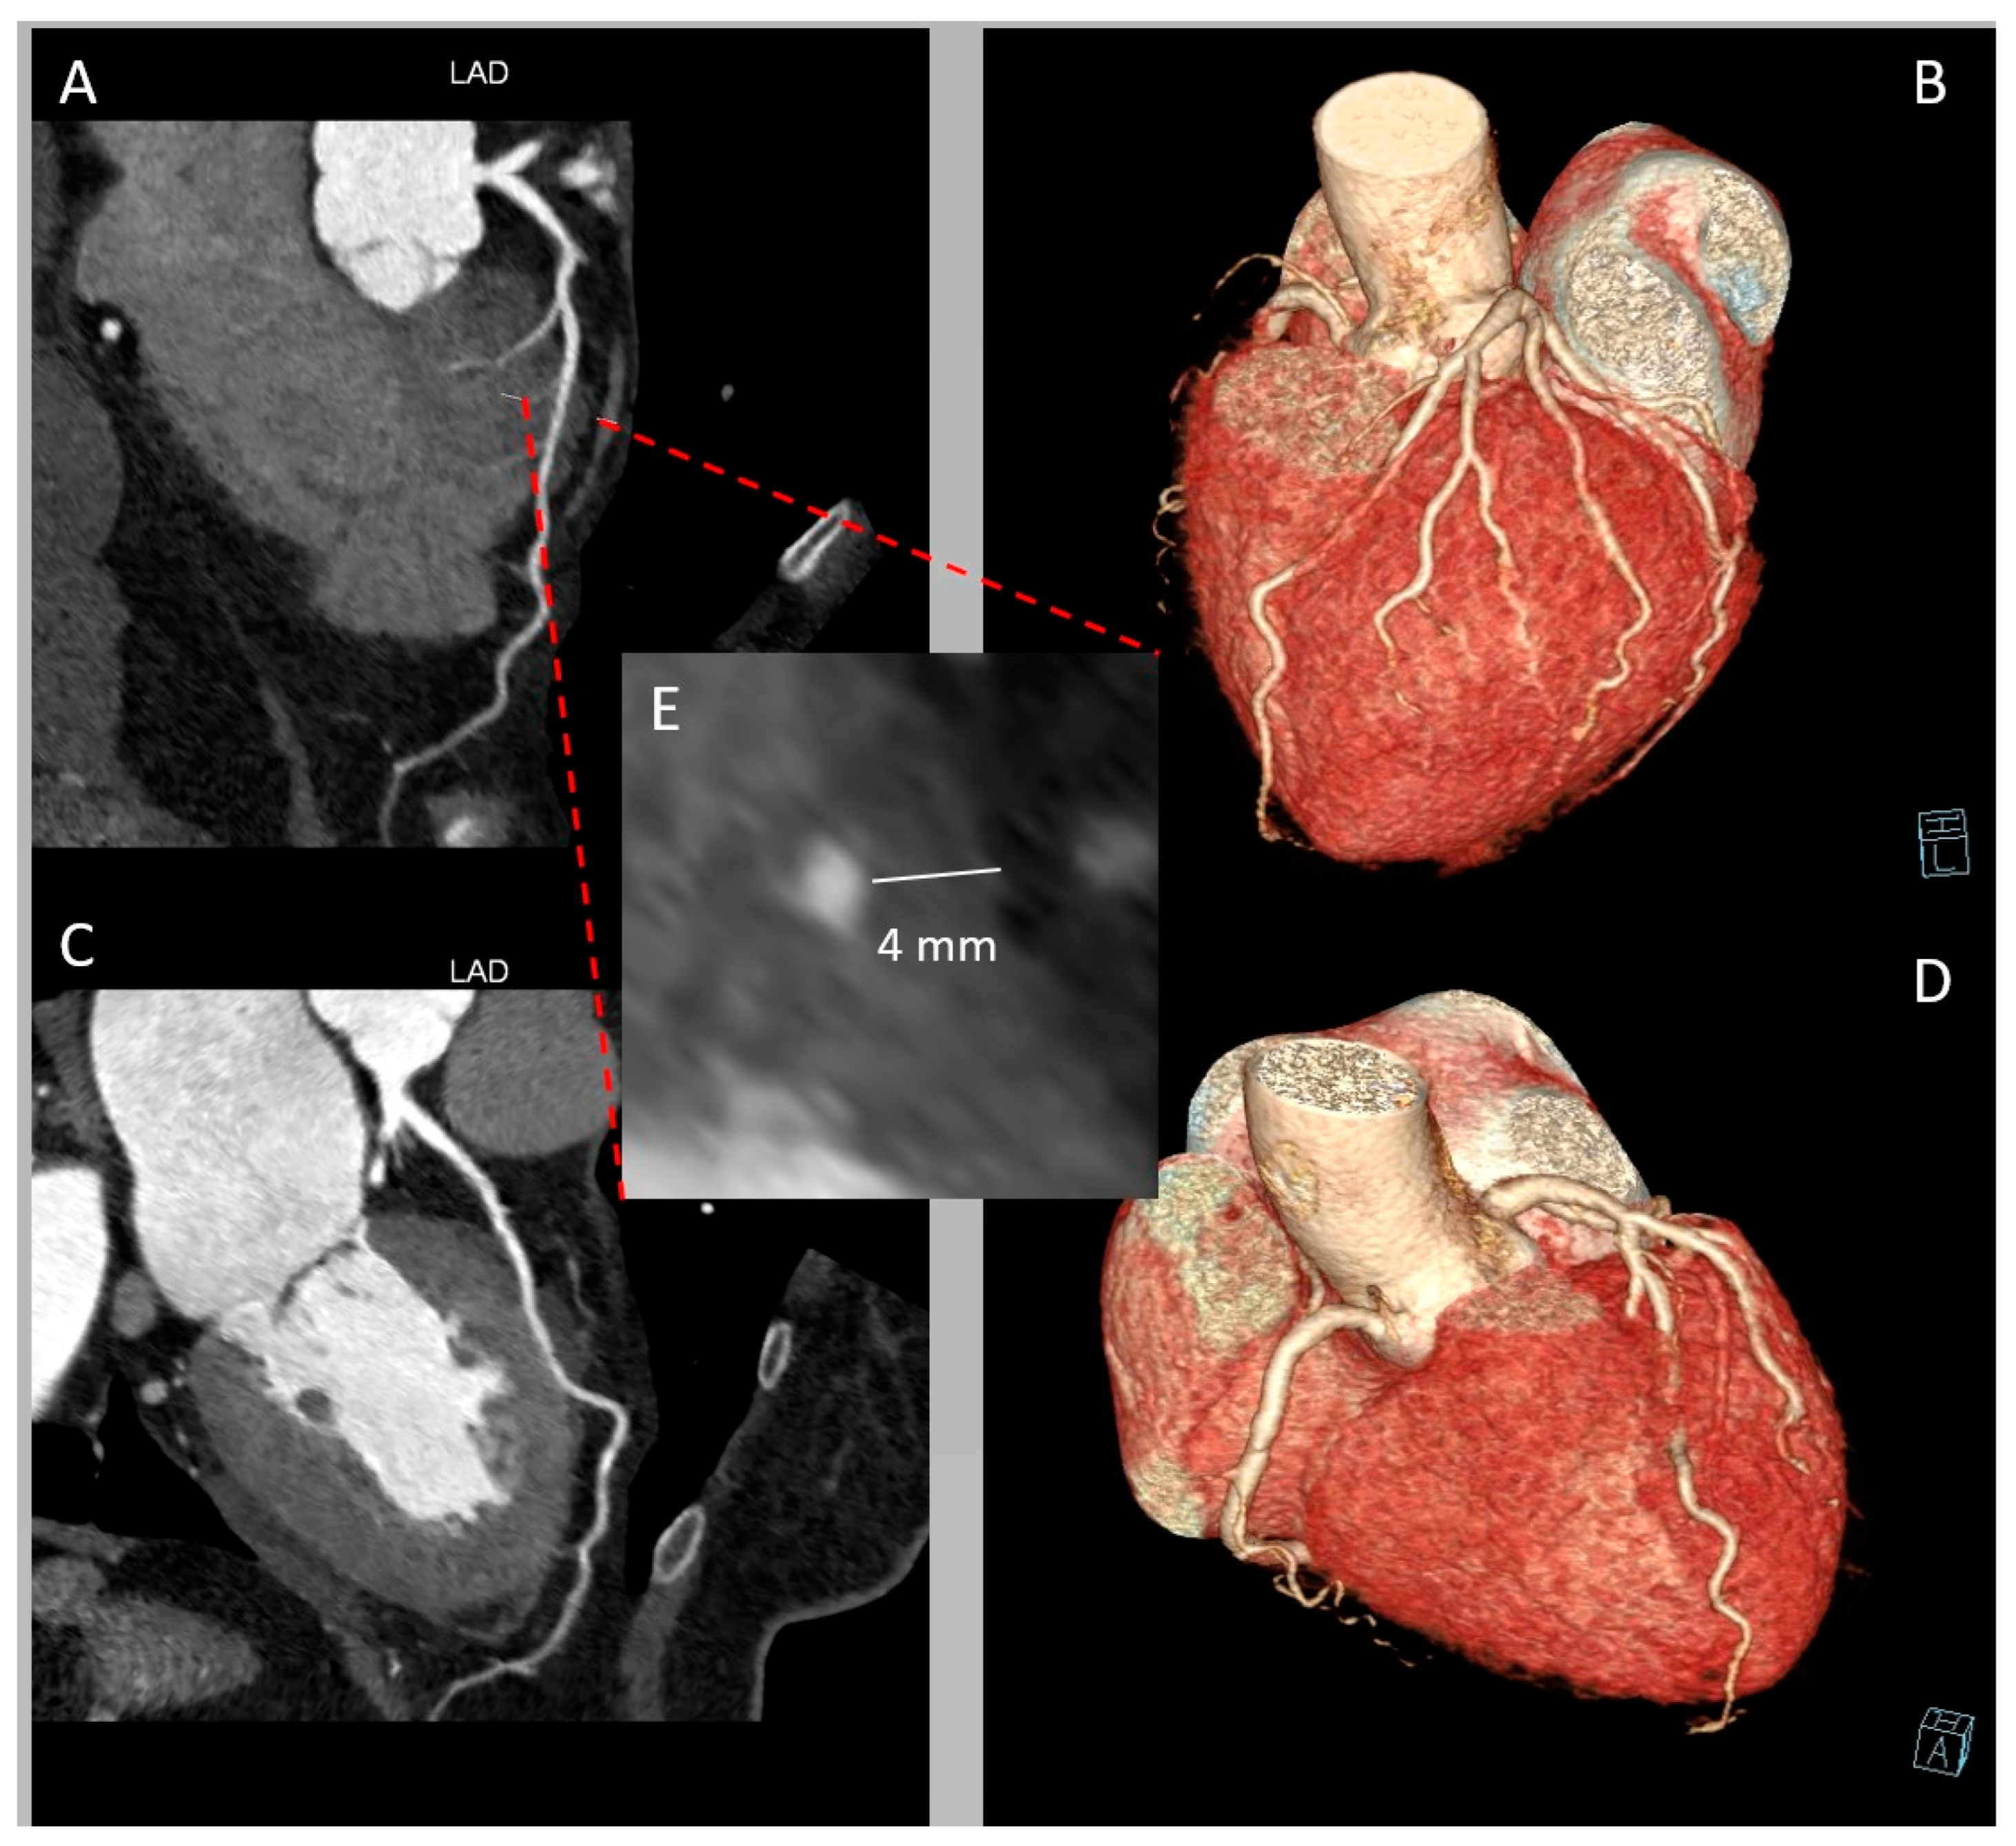

2. CCTA Imaging Protocol

3. Role of CCTA: Anatomical Evaluation